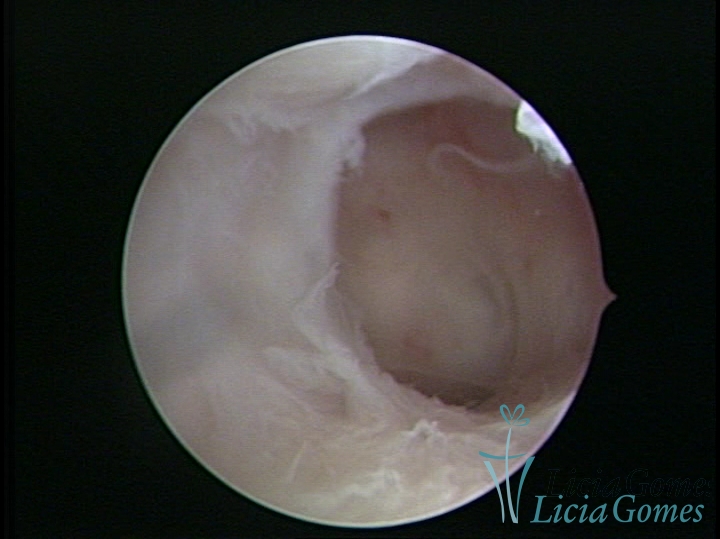

FIBROUS SYNECHIA

Uterine synechiae are scars (adherence) between the surface of the uterine walls, which may occur after the surgical procedure, uterine curettage, or after an inflammatory process in the uterine cavity (endometritis), which may lead to menstrual changes, infertility and obstetric complication such as abortion and premature birth.